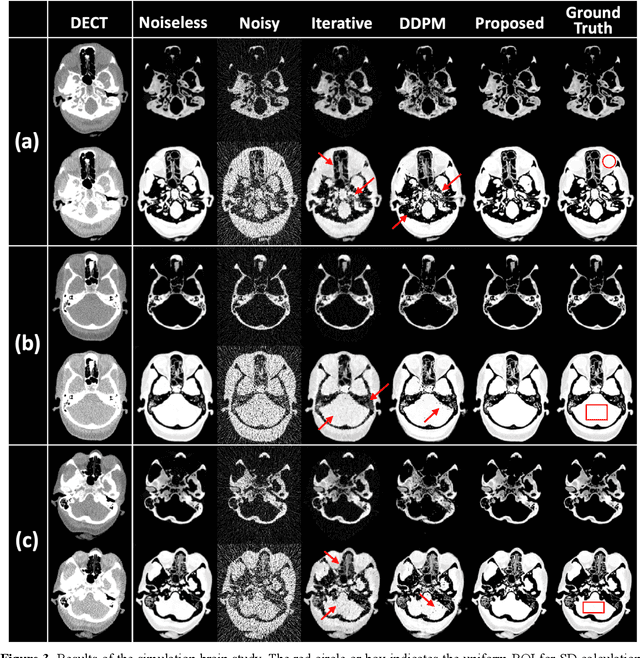

Abstract:Background: Dual-energy CT (DECT) and material decomposition play vital roles in quantitative medical imaging. However, the decomposition process may suffer from significant noise amplification, leading to severely degraded image signal-to-noise ratios (SNRs). While existing iterative algorithms perform noise suppression using different image priors, these heuristic image priors cannot accurately represent the features of the target image manifold. Although deep learning-based decomposition methods have been reported, these methods are in the supervised-learning framework requiring paired data for training, which is not readily available in clinical settings. Purpose: This work aims to develop an unsupervised-learning framework with data-measurement consistency for image-domain material decomposition in DECT.